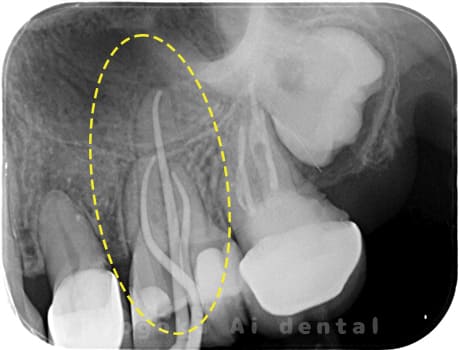

根管内の異物

- 原因

- 根管内異物(ファイル破折)による慢性根尖性歯周炎

- 治療期間

- 3ヶ月

- 治療内容

- マイクロスコープを使用した根管内異物除去並びにマイクロエンド

- 治療費用

- 121,000円(ファイル除去費用も込み)

他院で細い器具(ファイル)が根管内に破折した状態で、咬合痛を主訴に来院された患者様です。ファイルをマイクロスコープ下で除去し、根管治療を行ないました。